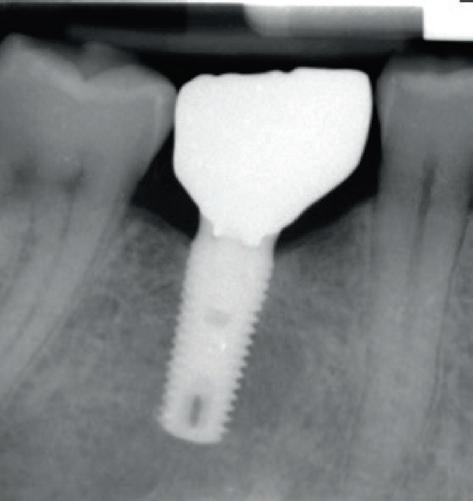

Each year, millions of people get dental implants as a longterm, natural-looking fix for missing teeth. But traditional implants don’t fully mimic real teeth.

Researchers from Tufts University School of Dental Medicine and Tufts University School of Medicine recently described a new approach to dental implants that could better replicate how natural teeth feel and function. Their study, published in Scientific Reports, shows early success with both a “smart” implant and a new gentler surgical technique in rodents.

“Natural teeth connect to the jawbone through soft tissue rich in nerves, which help sense pressure and texture and guide how we chew and speak. Implants lack that sensory feedback,” said Jake Jinkun Chen, DI09, a professor of periodontology and director of the Division of Oral Biology at the School of Dental Medicine and the senior author on the study.

Traditional dental implants use a titanium post that fuses directly to the jawbone to support a ceramic crown, and the surgery often cuts or damages nearby nerves. To tie these inert pieces of metal into the body’s sensory system, the Tufts team developed an implant wrapped in an innovative biodegradable coating. This coating contains stem cells and a special protein that helps them multiply and turn into nerve tissue. As the coating dissolves during the healing process, it releases the stem cells and protein, fueling the growth of new nerve tissue around the implant.

The coating also contains tiny, rubbery particles that act like memory foam. Compressed so that the implant is smaller than the missing tooth when it’s first inserted, these nanofibers gently expand once in place until the implant snugly fits the socket. This allows for a new minimally invasive procedure that preserves existing nerve endings in the tissue around the implant.

Siddhartha Das et al, Surgical considerations towards inducing proprioceptive feedback in dental implants, Scientific Reports (2025). DOI: 10.1038/s41598-025-99923-8